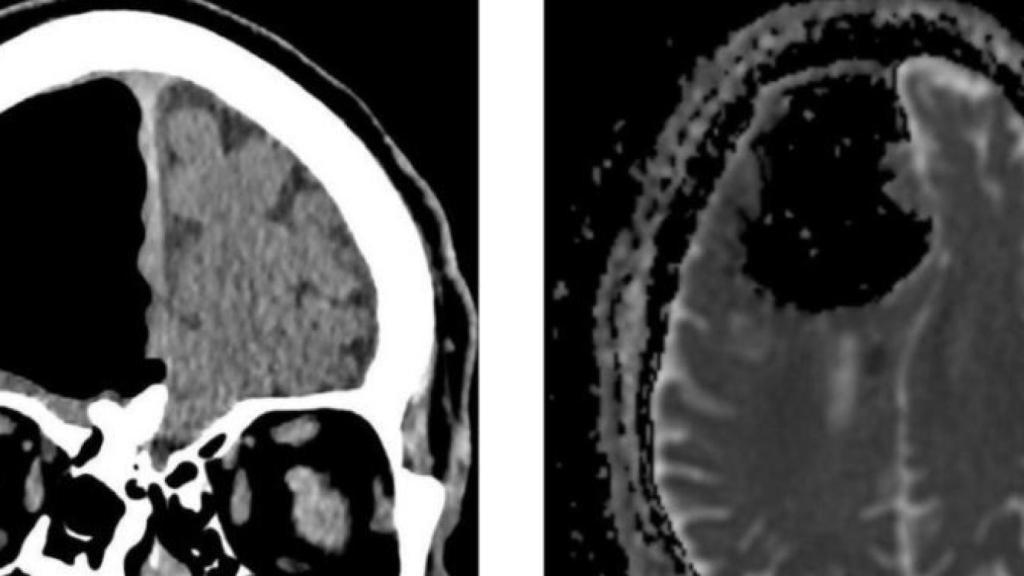

Imagen del TAC con el agujero y la lesión. BMJ Case Reports.

Cuando un hombre de 84 años en Irlanda se presentó ante el médico quejándose por sufrir inestabilidad, los especialistas encontraron una extraña razón para esa nueva torpeza. La tomografía computarizada del cerebro (TAC) que se le realizó al paciente mostró que una gran parte de su lóbulo frontal derecho parecía no existir.

El aumento de pérdida de equilibrio y la debilidad unilateral presentes al mismo tiempo pueden ser síntoma de un accidente cerebrovascular, por lo que los médicos prescribieron al paciente una tomografía computarizada (TAC). El resultado fue desconcertante: un gran agujero negro, de nueve centímetros de ancho, donde debería estar el lóbulo frontal derecho.

Una resonancia magnética confirmó que la materia cerebral del hombre en realidad no había desaparecido; más bien, tenía una cavidad de aire dentro de su cráneo llamada pneumatocele.

La resonancia magnética también reveló la presencia de un osteoma, un tipo común de tumor óseo benigno, en el hueso etmoidal, que separa la cavidad nasal del cerebro. Esta parte erosionada del hueso permitió que el aire entrara a su cráneo bajo lo que los médicos llamaron un "efecto de válvula de una sola vía". Esto puede ser una complicación rara, pero no desconocida, del osteoma sinusal. Sin embargo, no era lo único que le pasaba al paciente; como habían sospechado sus médicos, resultó que también sufría un derrame cerebral leve.